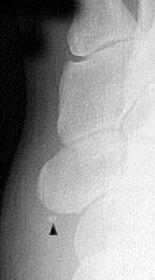

| What disease is this? What does the arrow indicate? | Rheumatoid arthritis. Arrow = Bone erosion secondary to inflammation of retrocalcaneal bursa. |